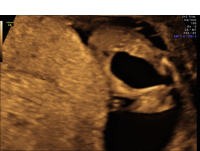

Luto keyhole bladder